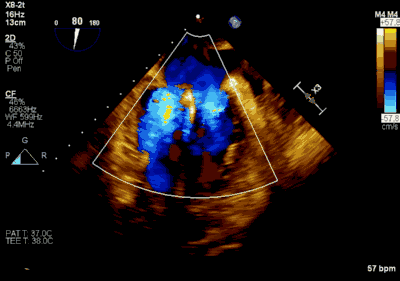

▲ 术前超声检查显示重度二尖瓣反流

患者为66岁老年男性,4个月余前因“急性心肌梗死合并二尖瓣后叶腱索断裂”出现心源性休克,在IABP支持下仍反复发作左心心力衰竭,经过急诊血运重建联合优化药物治疗后症状好转,但术后多次发作严重左心心力衰竭,超声心动图评估二尖瓣反流急性增加至极重度,左房、左室显著扩大。此次主诉“反复胸闷、气促4月余”入院。诊断:心脏瓣膜病 二尖瓣脱垂伴重度关闭不全 二尖瓣后叶腱索断裂 心功能IV级(NYHA分级) 。术前经胸超声心动图示:全心扩大,二尖瓣后叶脱垂、腱索断裂合并重度关闭不全(DMR 4+)。心脏测值:LA 45mm LVD 55mm EF% 61% PASP 82mmHg。经食管超声心动图示:二尖瓣环左右径33mm,反流束缩流颈宽度为5.5mm,EROA 0.67cm2(PISA),舒张期二尖瓣口平均跨瓣压差5mmHg。

患者全麻以后,在经食道超声心动图和X射线引导下,经股静脉入路,将MitraClip瓣膜夹顺利送至二尖瓣前后叶交界中心处,成功捕捉二尖瓣前叶A2和后叶P2,经超声心动图反复确认瓣叶夹持牢固后,测定有效夹持长度10.4mm,评估反流量降至轻度,释放瓣膜夹,超声心动图评估瓣膜夹位置和功能良好,测定左房压降至26/12mmHg,再次评估反流量仍为轻度,手术顺利完成。